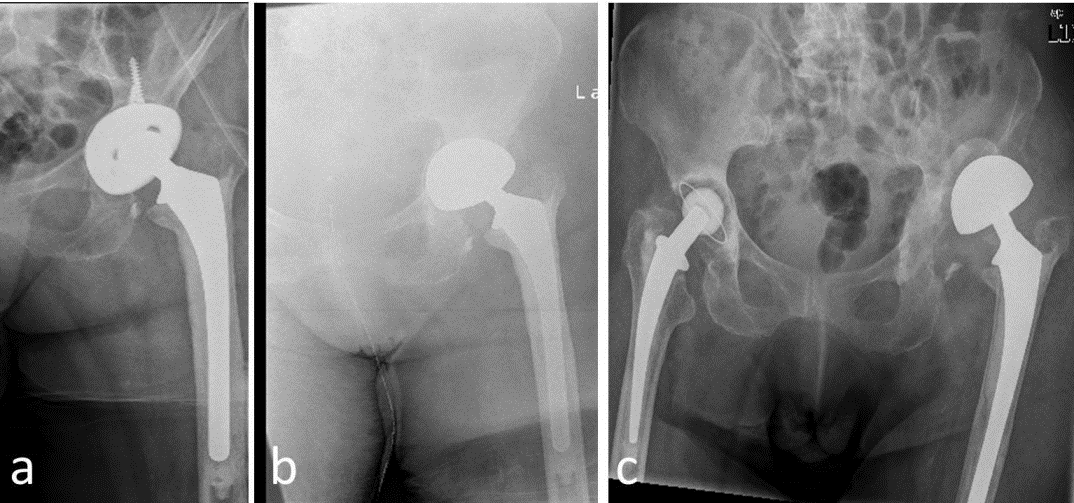

Figure1: 72-year-old patient, ASA 3, intraoperative significant acetabular bone defects. Uncomplicated postoperative course. Improvement of the Harris Hip Score from 39 preoperatively to 74 two years after revision surgery.

a. aseptic loosening of the acetabular cup, b. immediate postoperative result, c. two years after surgery